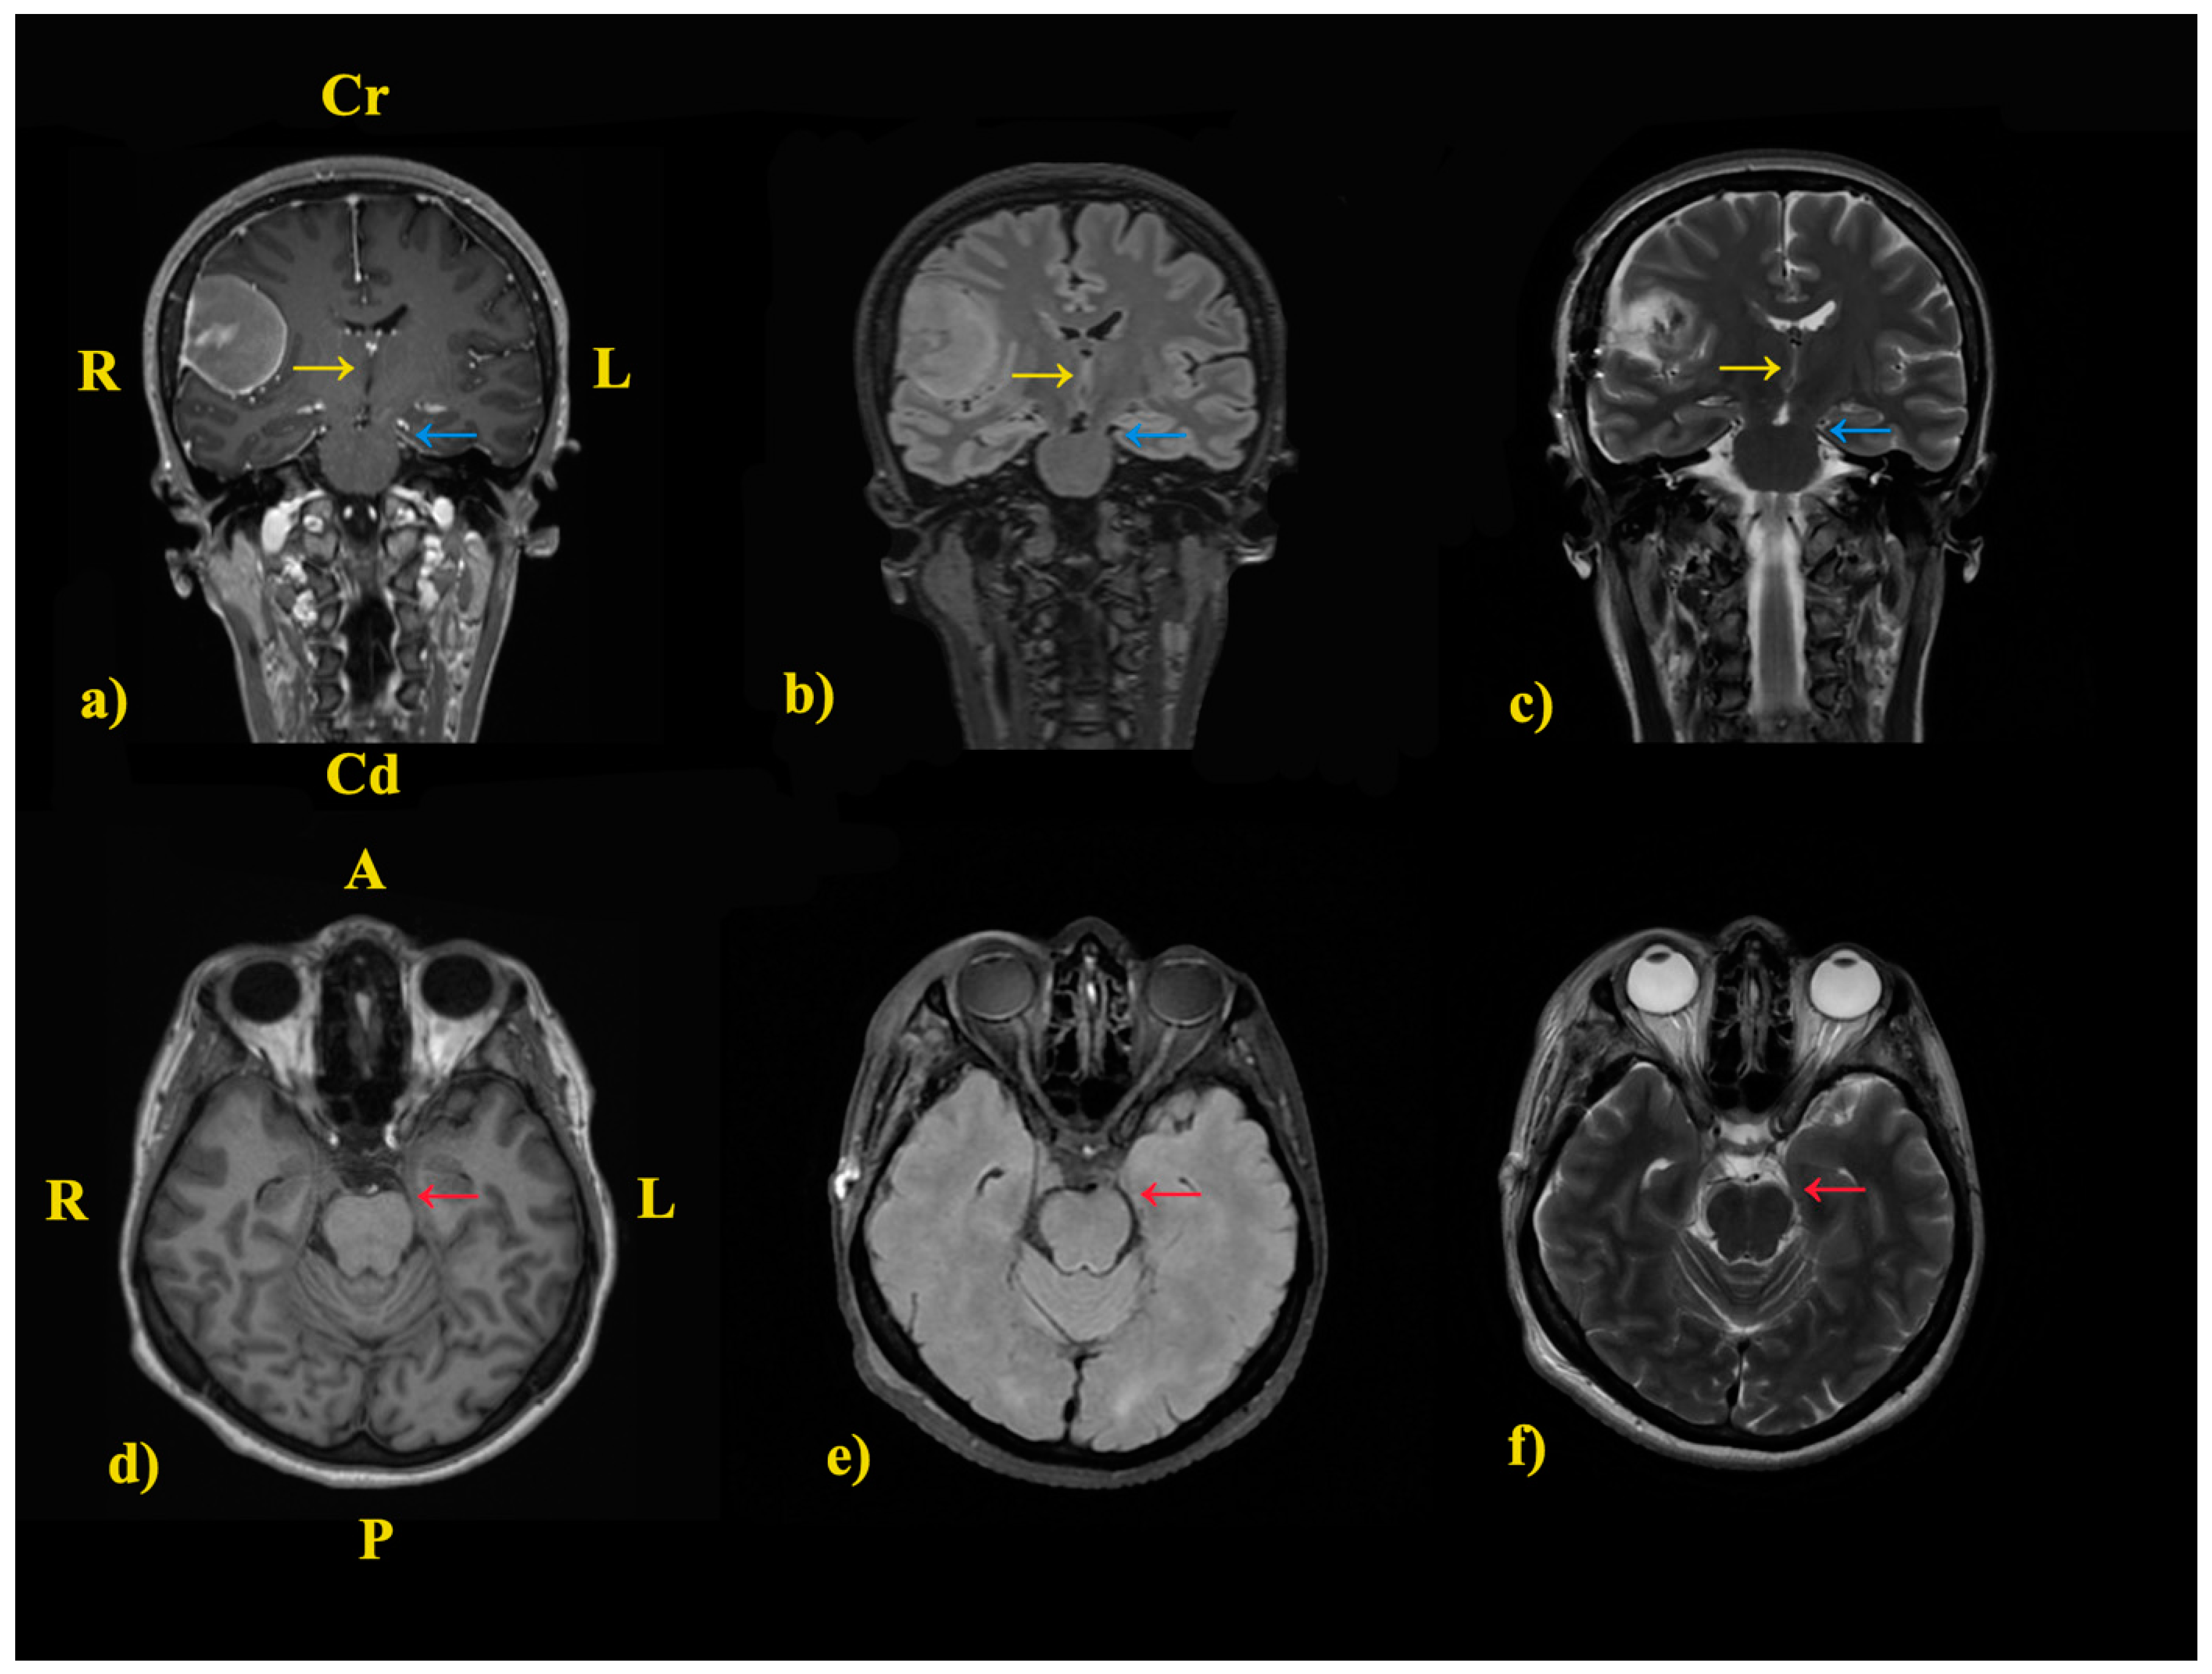

2. The Case: An Intriguing Case Unraveling Clinical and Paraclinical Complexities

3.1. Pathophysiological Hypotheses

3.1.3. Kernohan-Woltman Notch Phenomenon (KWNP)

3.2. Discussions of a Rare Encounter: What Is the Possible Cause of IH in Our Case?